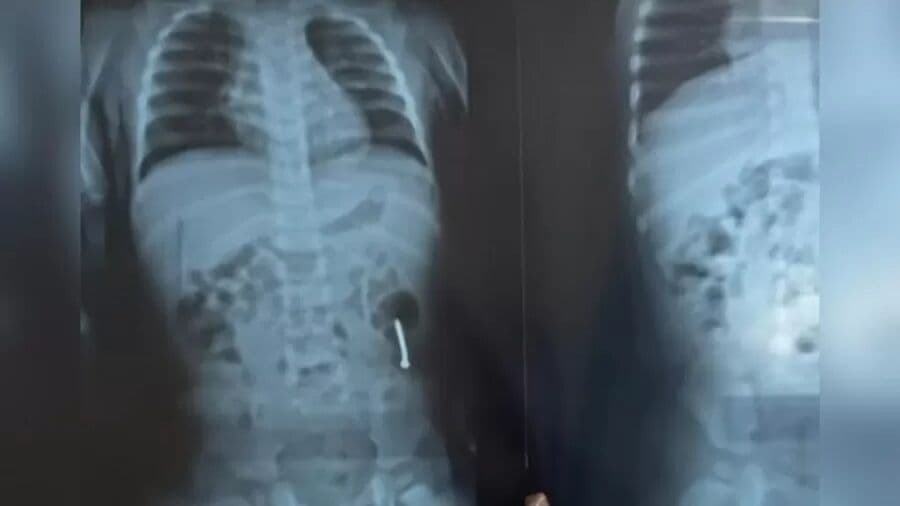

Menina de um ano é internada após engolir prego no dia do aniversário no Pará